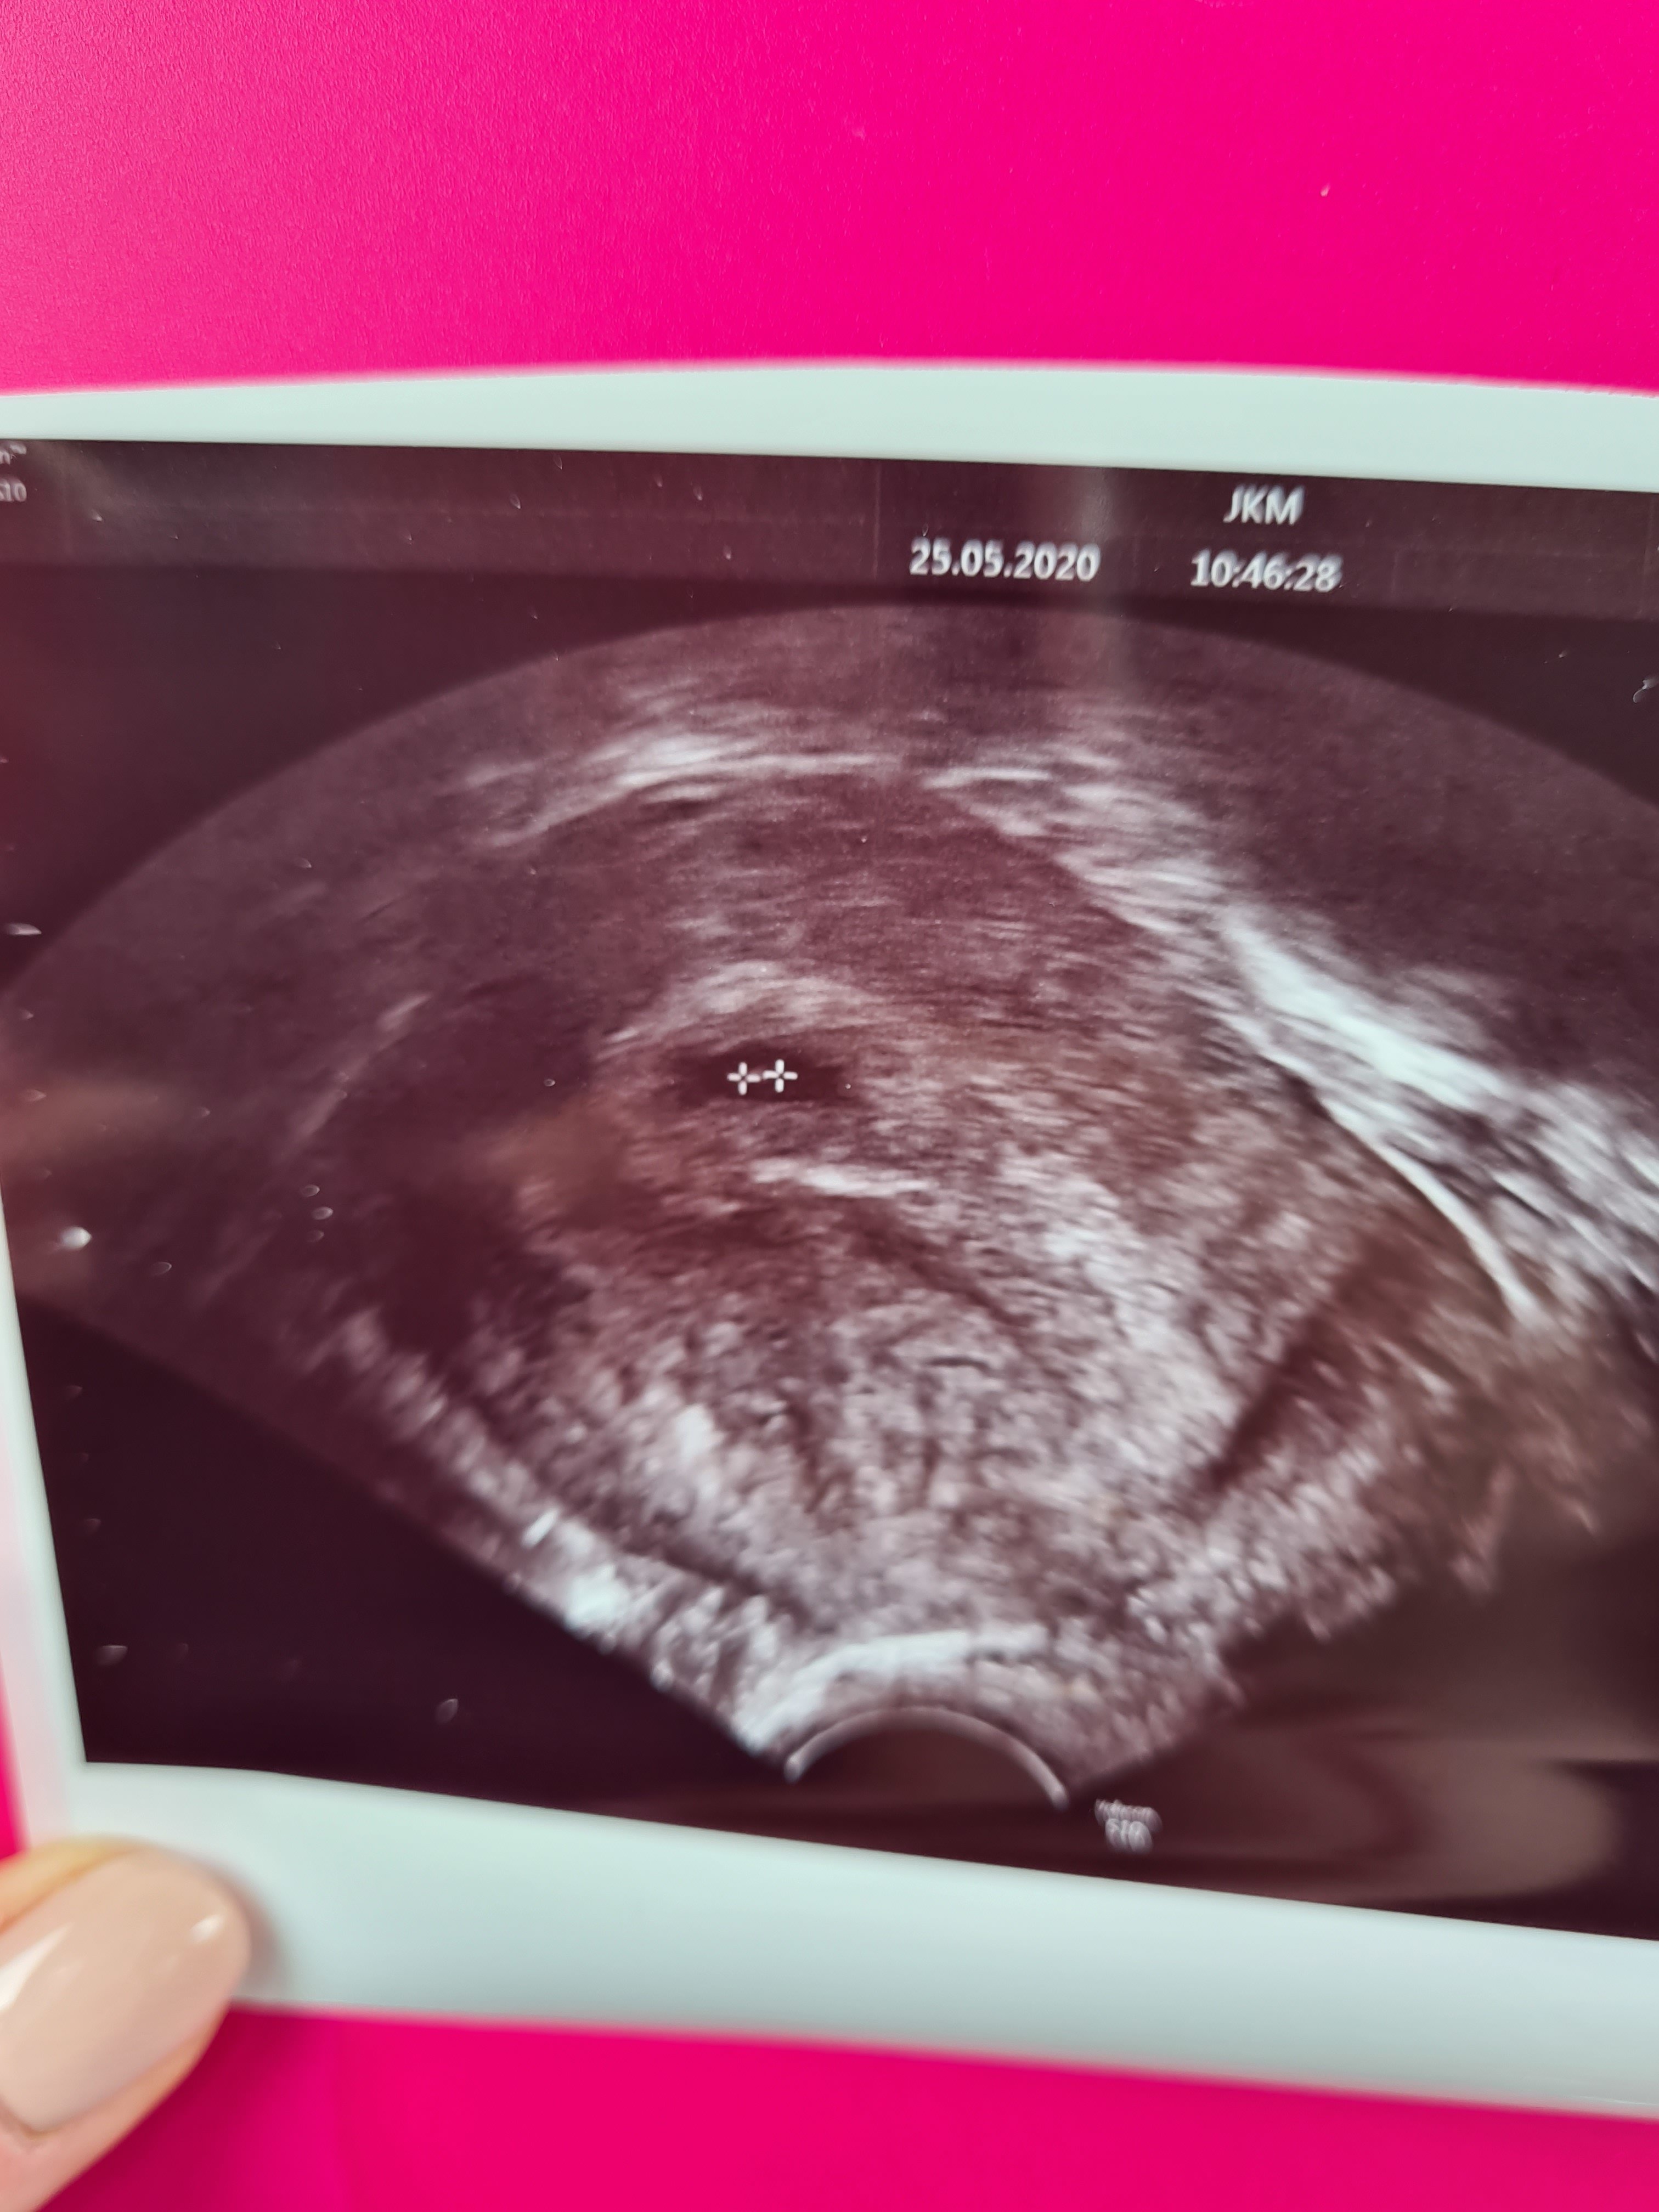

Dziewczyny jestem dziś po wizycie. Mlodziutka ciąża, widac bylo cialko zolte i zarodeczek malutki jeszcze bez serduszka. Nastepna wizyta za 2 tygodnie. Mam nadzieję, ze już wszystko bedzie ladnie widać. Zdjecie z usg zalączam. Dzis jestem 5+4.

Lekarka mowila ze bedzie dobrze, zeby sie nie martwic. Poki co jest bardzo wcześnie, musze poczekać do 8 czerwca jeszcze cierpliwie.. Ciąża daje mi sie juz we znaki, mdlosci, zgaga okrutna wiec jest wszysto ok.Malwa to chyba dobre informacjena ten czas ciąży wszystko jest dobrze